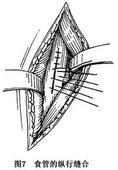

食管腐蚀伤

628健康网为您分享有关食管腐蚀伤的症状,食管腐蚀伤的治疗方法,食管腐蚀伤的预防知识,食管腐蚀伤的症状图片,食管腐蚀伤...